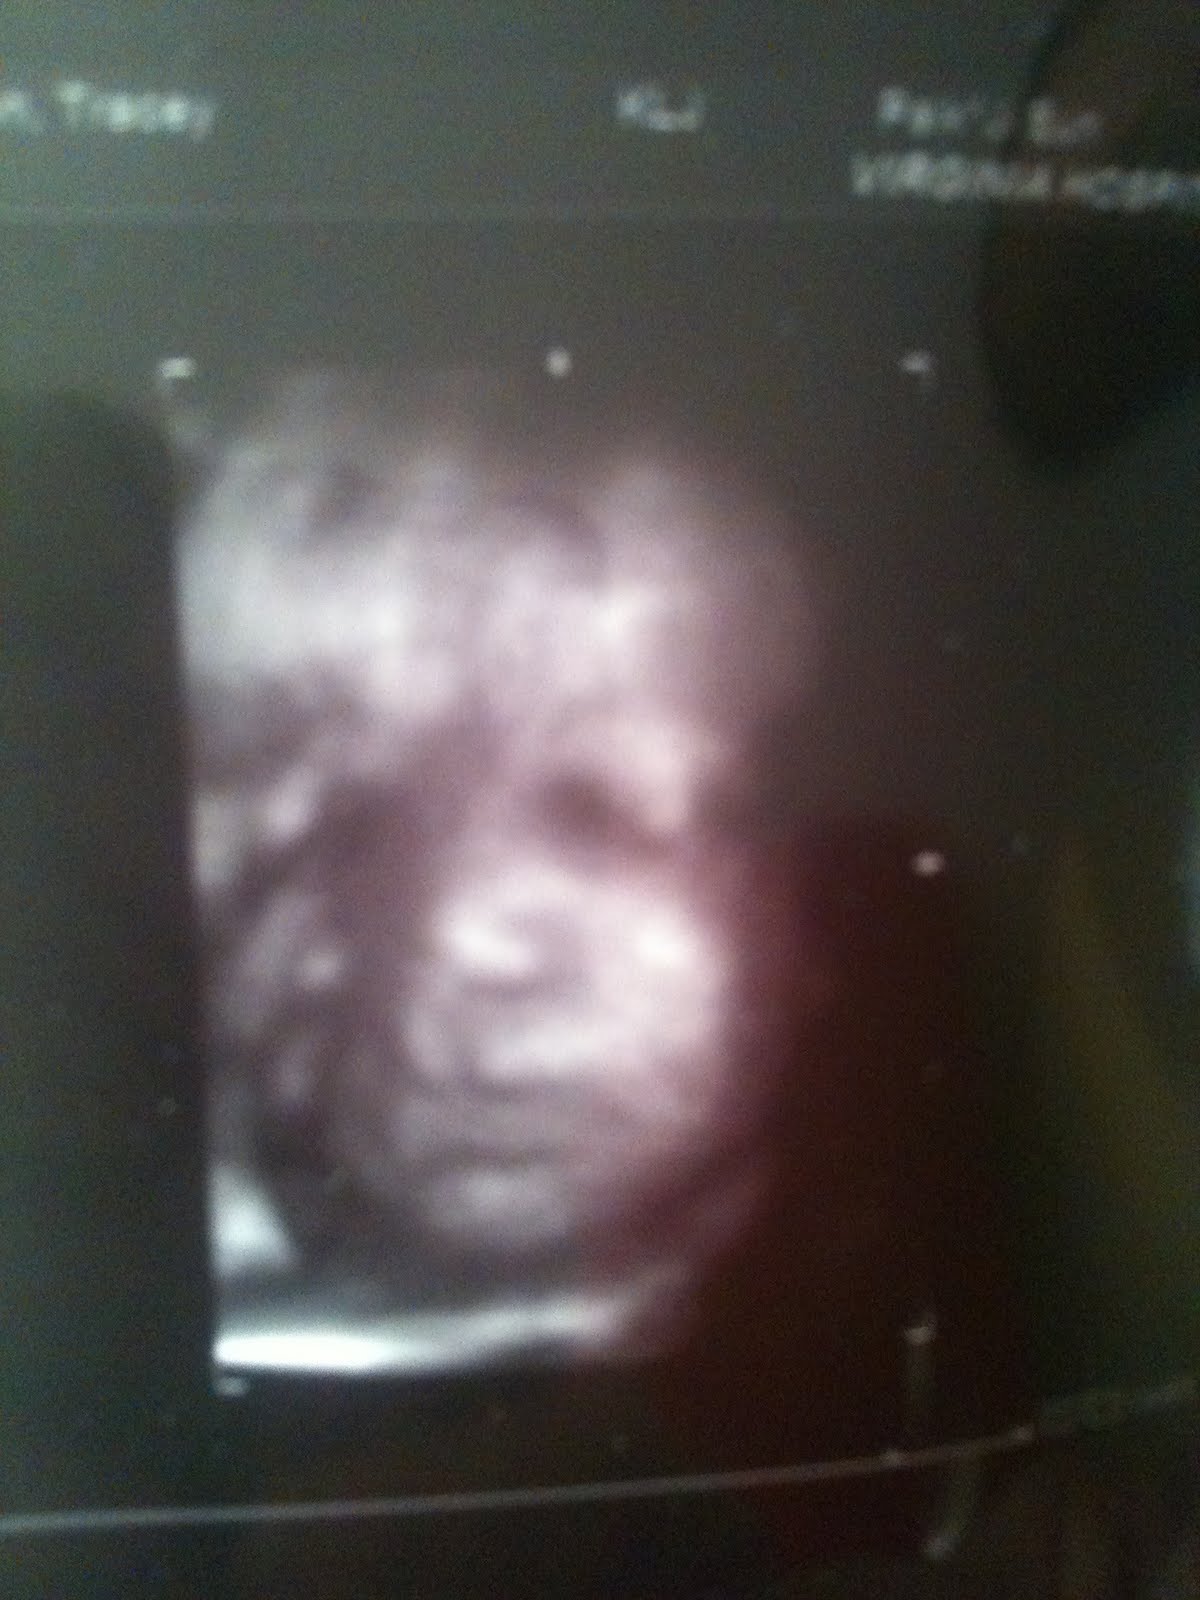

Getting back to the ultrasound, all of the sudden I look up on the screen and see a FACE! It was Sofia's face!!! I had no idea that regular machines could produce a 3D/4D image!!! And I had no clue that the tech was going to turn it on, but there she was staring back at me! So crazy and so beautiful! She has super chubby cheeks and is just adorable. She was able to get one good shot for me to take home and here it is!

That's our baby girl!! Her right hand is on the right side of her face...ahhh, I could look at her all day!